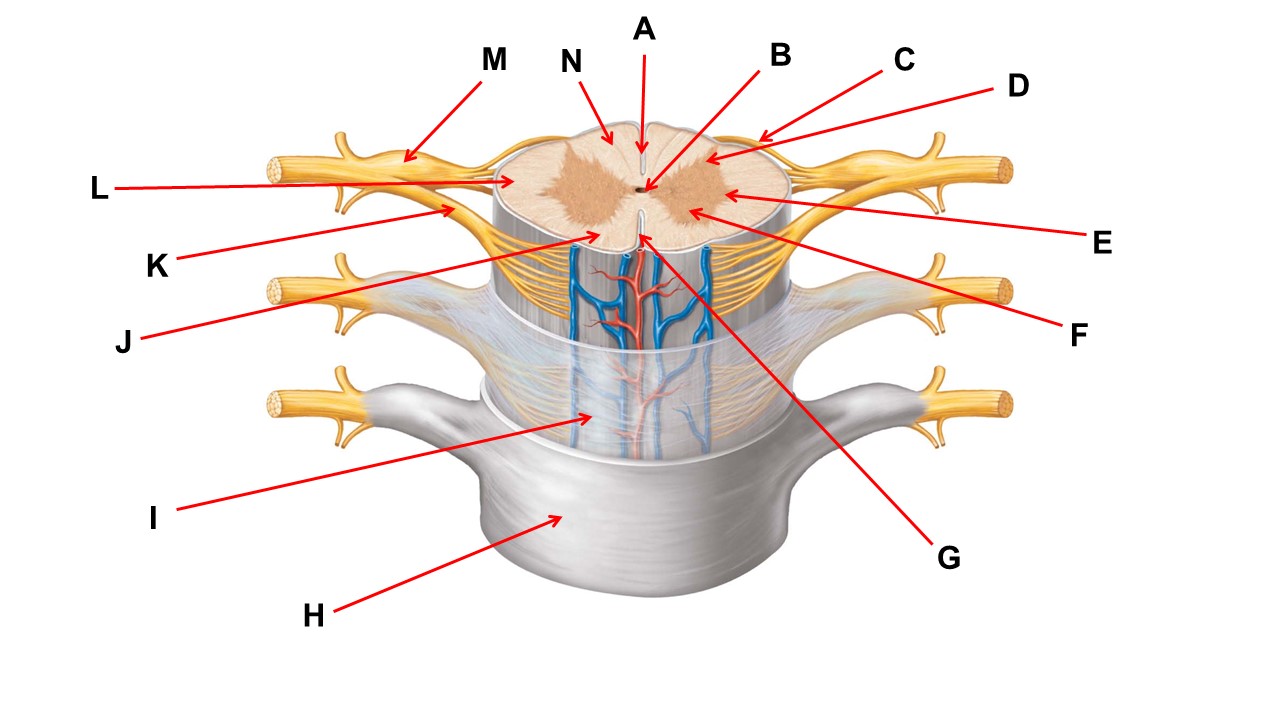

Name the region within bracket D.

Name the region of tissue surrounding the tip of arrow E.

Name the region of tissue surrounding the tip of arrow B.

dorsal horn

Name the structure at the tip of arrow K.

ventral root

Name the region of tissue surrounding the tip of arrow J.

ventral column

Name the region of tissue surrounding the tip of arrow E.

lateral horn

Name the region of tissue surrounding the tip of arrow N.

dorsal column

Name the deep groove at the tip of arrow G.

anterior median fissure

Which structure(s ) would be found in the area at the tip of arrow D.

cell bodies of interneurons

Name the region of tissue surrounding the tip of arrow E.

ventral horn

Name the region within bracket G.

gray commisure